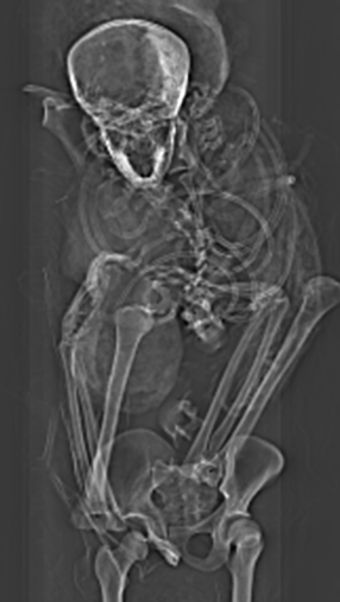

En la actualidad, un equipo de científicos, dirigido por Sahar Saleem, profesor de radiología en la Universidad de El Cairo, realizó tomografías para volver a analizar la momia, conservada en el Museo Egipcio de El Cairo. El nuevo estudio dejó ver que la momia está en muy mal estado. La cabeza desconectada del cuerpo, vértebras y costillas sueltas, y muy poco tejido blando.

La posición de las manos del rey refieren al “espasmo cadavérico” que afecta las extremidades de las personas sometidas a muertes violentas. Al parecer las manos del faraón estaban atadas cuando lo mataron y es algo que explicaría la ausencia de heridas defensivas en sus manos o brazos.